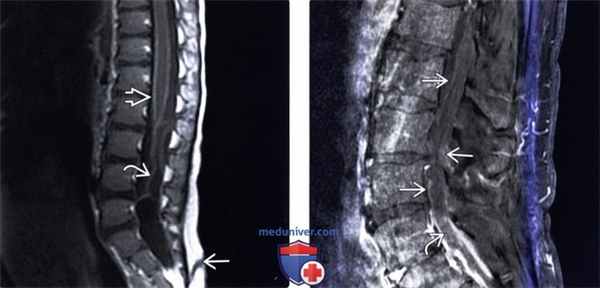

(Слева) МР-И: диффузное усиление сигнала мягкой мозговой оболочки и конского хвоста на фоне менингита. Минимальным контрастным усилением сигнала характеризуется и имеющий место в данном случае эпидермоид. В области крестца виден дорзальный эпителиальный ход.

(Справа) Утолщение и контрастное усиление сигнала конского хвоста в этом случае связано с адгезивным арахноидитом. Фибринозный экссудат с минимальной клеточной инфильтрацией в подобных случаях приводит к формированию спаек между листками паутинной оболочки и корешками спинного мозга. Фибробласты, инфильтрирующие фибриновые свертки, продуцируют коллагеновые волокна. Рубцово-спаечный процесс может быть причиной изменения ликвородинамики.